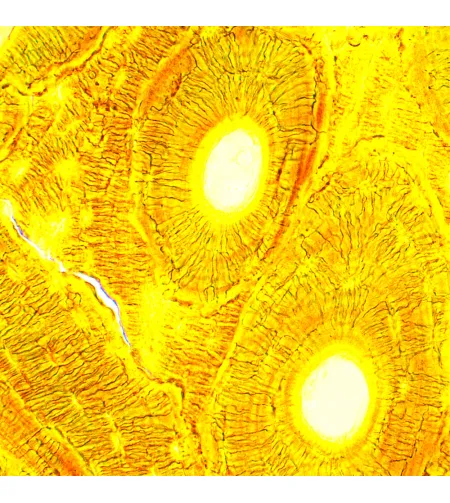

The MAGUS Bio D250T biological microscope is a professional instrument for observing biological specimens in transmitted light. The primary observation technique is a brightfield technique (ready-to-use). Darkfield, polarization, and phase contrast techniques are also available, but they require additional microscope accessories. The microscope is excellent for laboratory and research observations in medicine, pharmaceuticals, forensics, agriculture, and other fields.

The MAGUS CDF50 digital camera is designed for the brightfield microscopy technique. It offers a low noise level and high light sensitivity.

The camera is equipped with a 2.1MP sensor and delivers realistic Full HD images (1920x1080px) when observing with 40x, 60x, and 100x objectives.

- SONY Exmor backlit color CMOS sensor provides low noise level and high light sensitivity even in low-light conditions. You will get clearer, brighter, and more color-saturated images